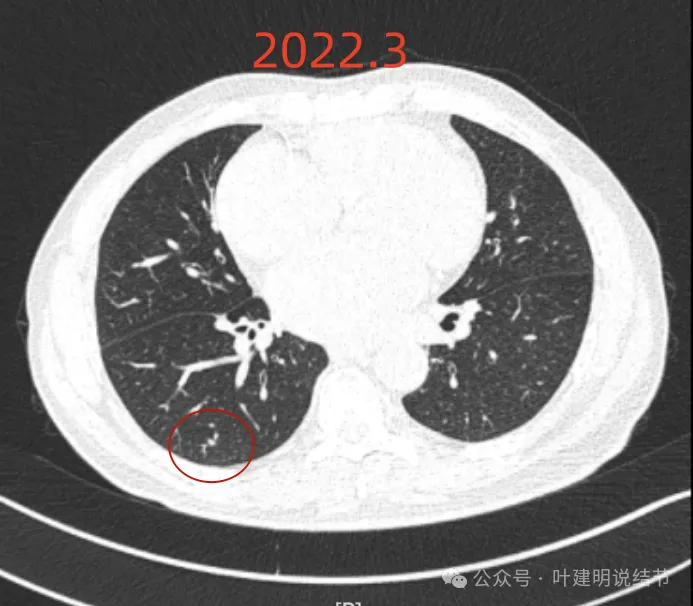

我们先来看2022年3月主要病灶的影像:

左下胸膜下实性结节,轮廓稍模糊,密度较高,边缘较光,像淋巴结些,能随访。